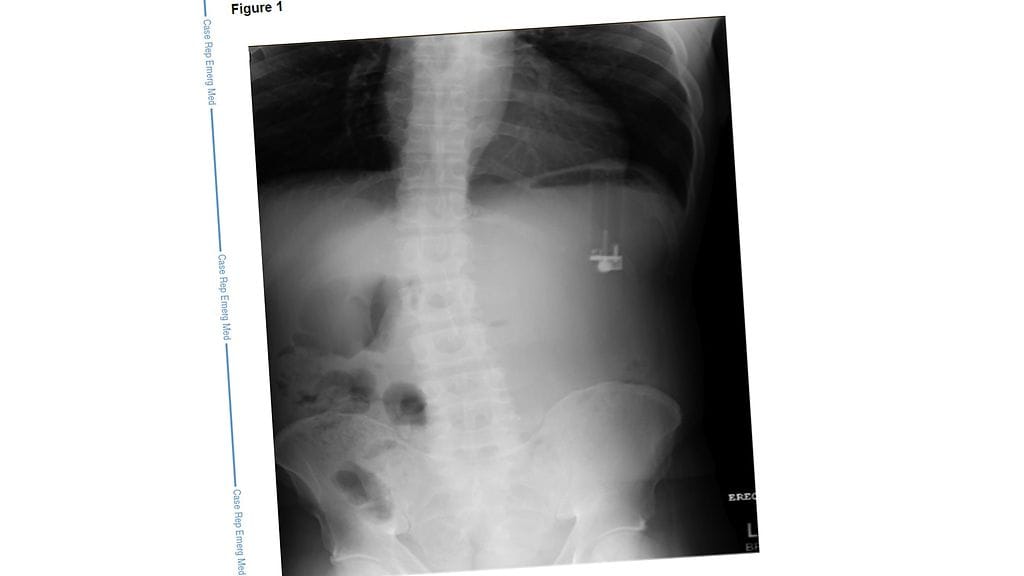

Floridalaisessa sairaalassa miehen veri- ja virtsakokeissa ei löydetty mitään poikkeavaa, mutta röntgenkuvaus paljasti miehen vatsasta vieraan esineen. Röntgenkuvassa näkyi selvästi ylösalaisin oleva tupakansytytin, jonka todettiin vuotavan myrkyllisiä kemikaaleja miehen suolistoon. Nämä kemikaalit olivat kehittäneet miehelle vuotamattoman mahahaavan, jonka läpimitta oli 5 millimetriä leveimmässä kohdassa.